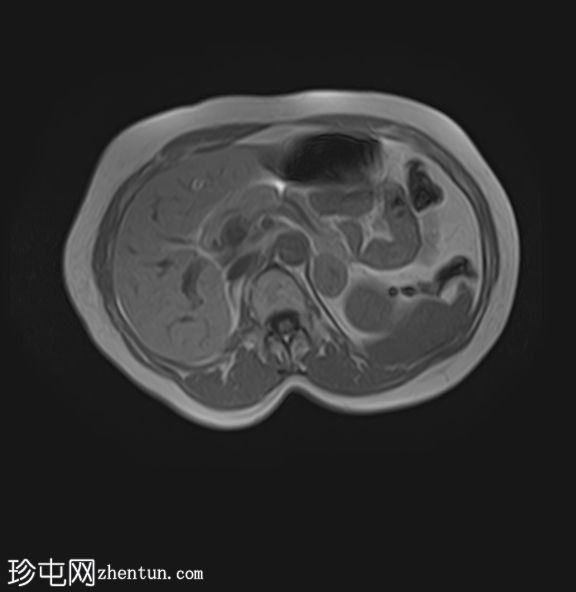

MRI

轴位T1加权像

(同相/反相)

轴位

T1加权像

脂肪抑制像

轴位T2加权像

STIR(FASE)序列

T2加权像

左侧肾上腺可见一边界清晰的病灶,大小约为3.0 × 2.4 × 2.0 cm。

化学位移成像显示,反相图像的信号强度较同相图像明显降低,与细胞内脂质含量相符。

右肾先天性缺失。左肾轻度肥大,信号强度正常。